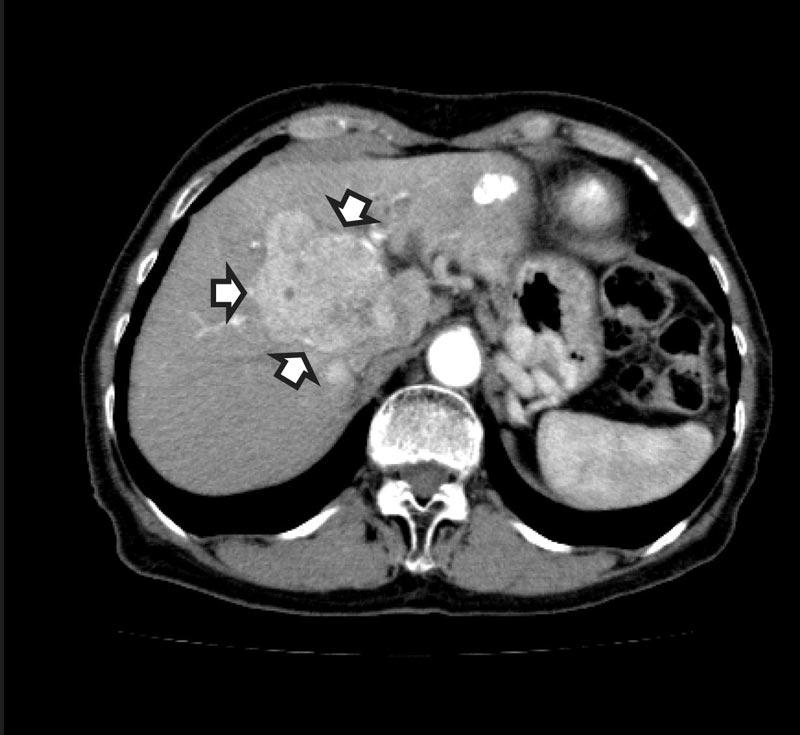

ผู้ป่วยมะเร็งตับระยะแรกมักไม่มีอาการ หรือมีอาการไม่เฉพาะเจาะจง แพทย์มักวินิจฉัยได้จากการตรวจคัดกรองในผู้ที่มีปัจจัยเสี่ยง เช่น การทำอัลตราซาวด์ หรือเอกซเรย์คอมพิวเตอร์พบก้อนมะเร็ง โดยส่วนใหญ่ถ้าผู้ป่วยมีอาการแล้ว โรคมะเร็งตับมักจะเป็นมากและลุกลาม อาการแสดงต่างๆ จะคล้ายกับผู้ป่วยที่เป็นโรคตับแข็ง เช่น ปวดท้อง เสียดท้อง น้ำหนักลด ตัวเหลือง ตาเหลือง ท้องบวมเนื่องจากมีน้ำในช่องท้อง ขาบวม อ่อนเพลีย ทานอาหารไม่ได้ อาเจียนเป็นเลือด

เนื่องจากมะเร็งตับเปรียบเหมือนมฤตยูเงียบ การเฝ้าระวังอย่างสม่ำเสมอจึงเป็นวิธีที่ดีที่สุด โดยเฉพาะในผู้ที่มีปัจจัยเสี่ยงต่อการเกิดมะเร็งตับ คือ ผู้ที่เป็นพาหะไวรัสตับอักเสบบีที่มีอายุเกิน 40 ปีขึ้นไปในผู้ชาย และอายุเกิน 50 ปีในผู้หญิง ผู้ป่วยที่มีภาวะตับแข็งจากทุกสาเหตุ ควรจะต้องตรวจอัลตราซาวด์ดูเนื้อตับอย่างน้อยทุก 6-12 เดือน